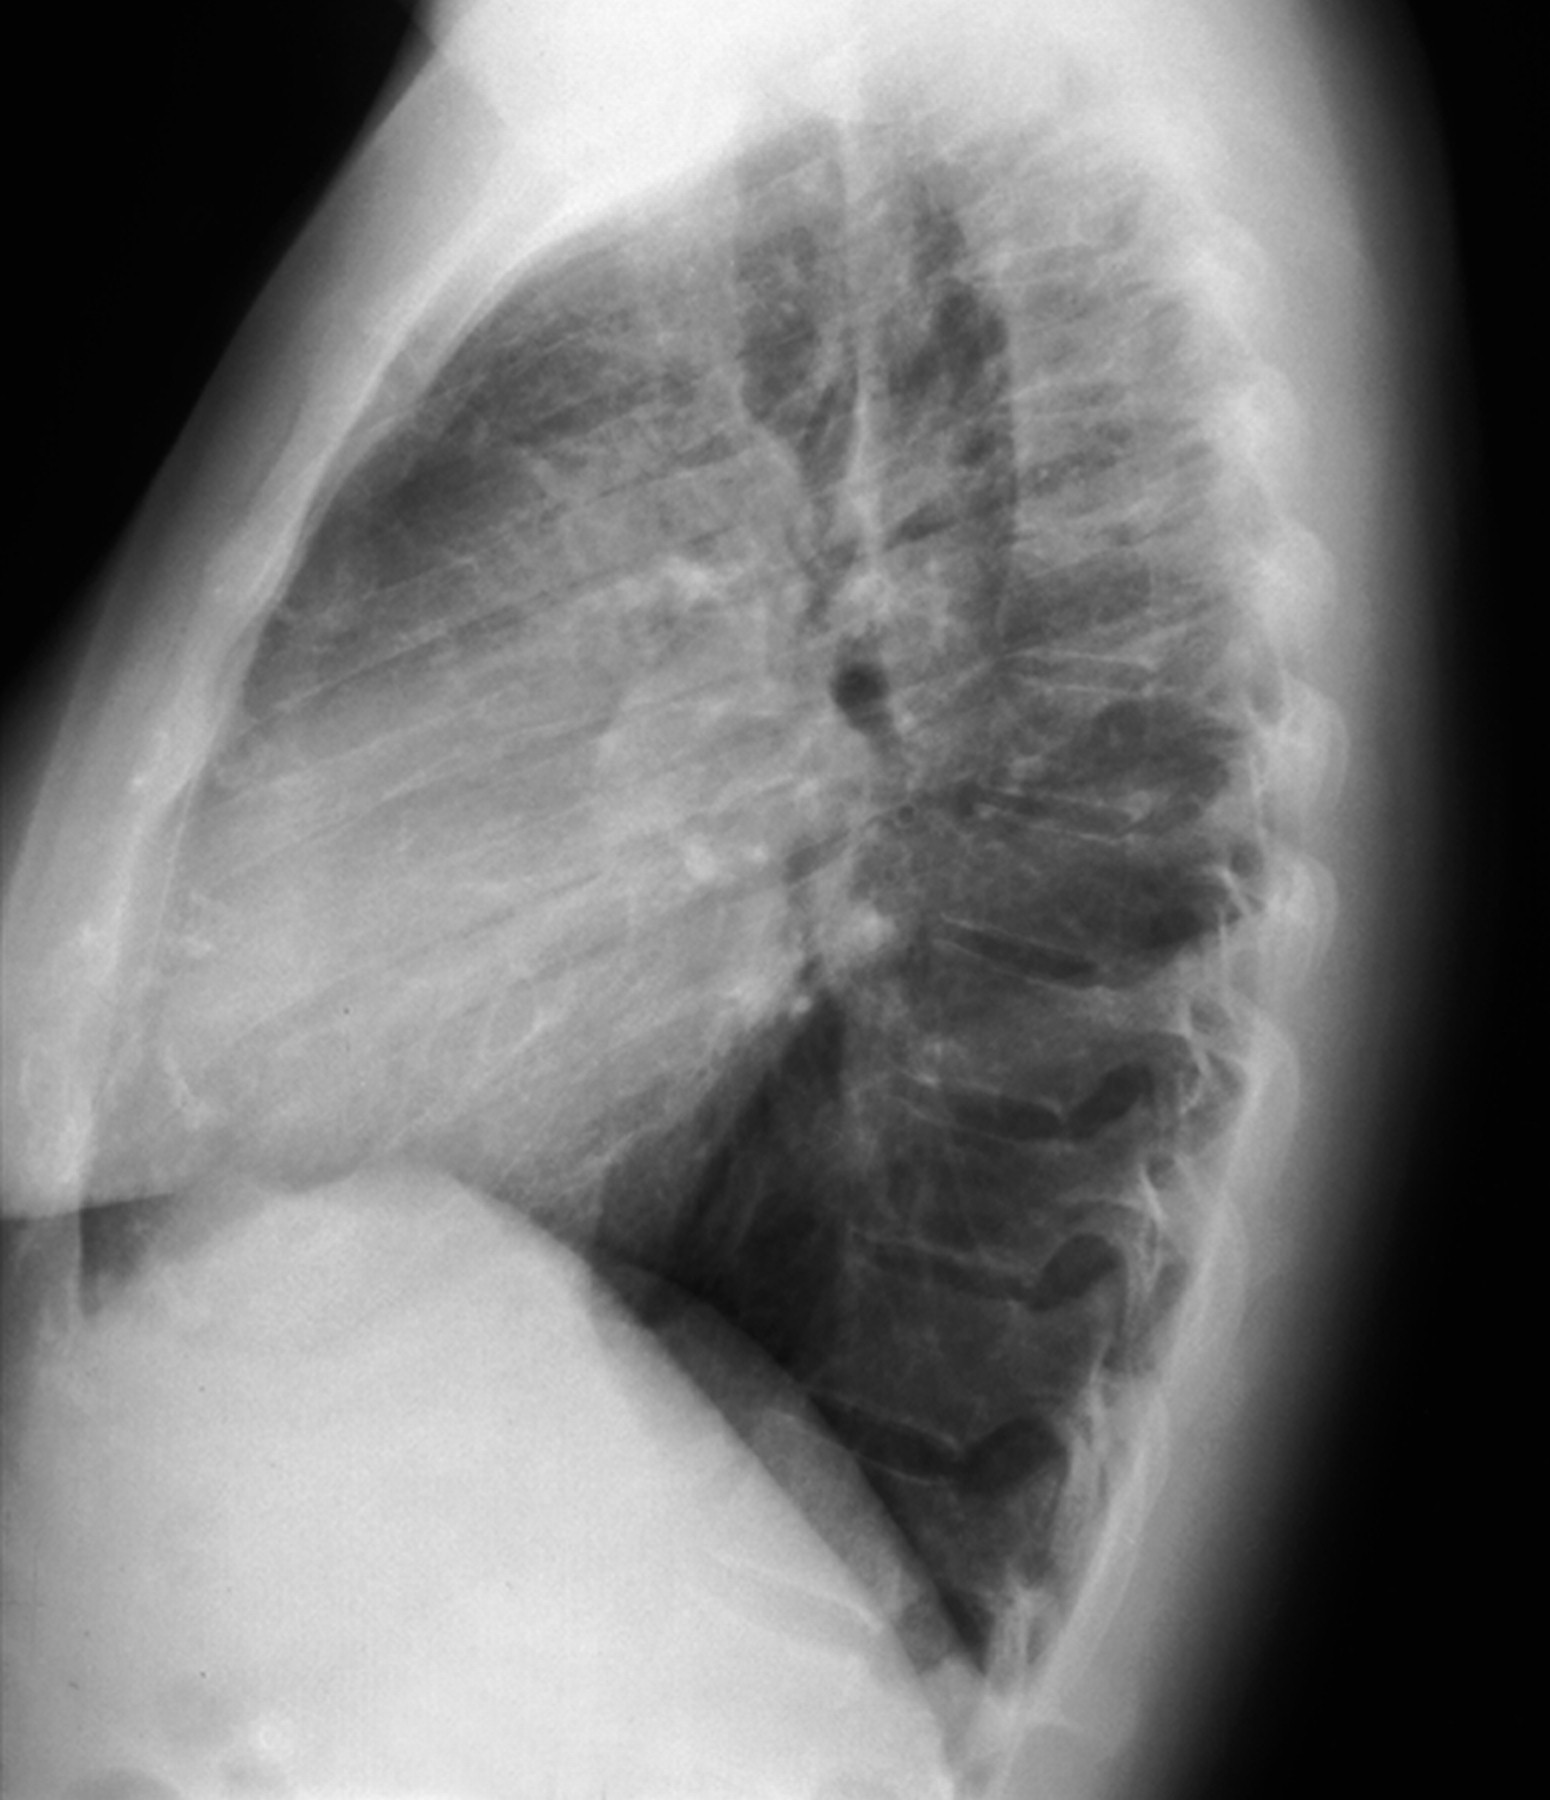

Особенностью рентгенологической картины при миксоме левого предсердия, если нарушения гемодинамики соответствуют митральному стенозу, является отсутствие выбухания ушка левого предсердия, полость левого предсердия расширена меньше, чем при митральном стенозе. При обызвествлении миксомы на рентгенограммах виден каль-циноз.